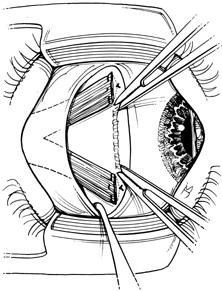

Step 2. A Stevens hook is brought from beneath the muscle to perforate it at its midpoint. Then, the hook is used to split the muscle into equal halves for a distance of 15 mm posterior to its insertion (Fig. 2). Blunt Westcott scissors may be used to complete the ends of the split, particularly at the muscle insertion (Fig. 3).

Fig. 2. A Stevens hook is brought from beneath the muscle to perforate it at its midpoint. Then, the hook is used to split the muscle into equal halves for a distance of 15 mm posterior to its insertion.

Fig. 3. Blunt Westcott scissors may be used to complete the ends of the split, particularly at the muscle insertion.

Step 3. Two double-armed 6-0 Vicryl sutures are used to secure each half of the muscle separately (Fig. 4). Both halves of the muscle are disinserted from the sclera (Fig. 5).

Fig. 4. Two double-armed 6-0 Vicryl sutures are used to secure each half of the muscle separately.

Fig. 5. Both halves of the muscle are disinserted from the sclera.

Step 4. The two halves of the muscle are separated into a Y configuration and reattached to the sclera as shown in Figure 6A. The inferior edge of the upper arm of the Y should be attached at the superior border of the original muscle insertion, and the superior edge of the inferior half of the muscle should be attached at the inferior border of the previous muscle insertion. If a recession is combined with the Y-splitting procedure, then these insertion points are relocated the desired amount posterior to the superior and inferior poles of the original insertion (Fig. 6B).

Fig. 6. The two halves of the muscle are separated into a Y configuration and reattached to the sclera. A. The inferior edge of the upper arm of the Y should be attached at the superior border of the original muscle insertion, and the superior edge of the inferior half of the muscle should be attached at the inferior border of the previous muscle insertion. B. If a recession is combined with the Y-splitting procedure, then these insertion points are relocated the desired amount posterior to the superior and inferior poles of the original insertion.